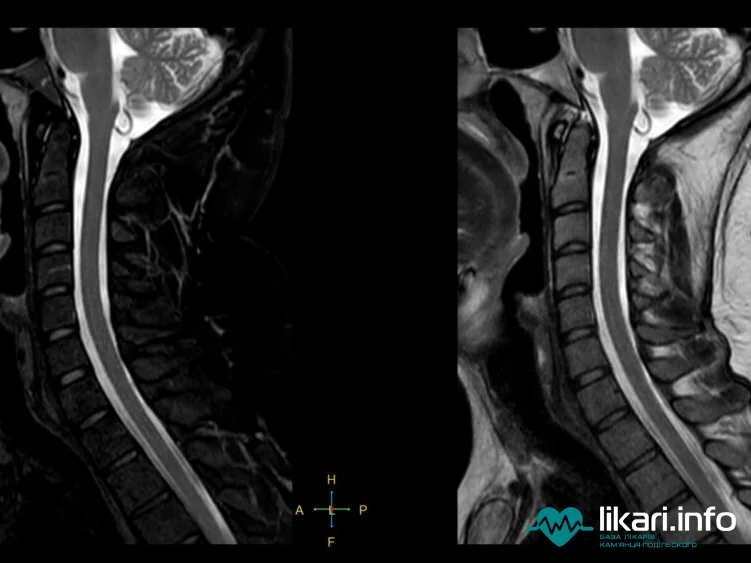

Магнітно-резонансна томографія (МРТ) шийного відділу хребта — це високоточний діагностичний метод, який використовується не стільки для встановлення первинного діагнозу, скільки для його уточнення та детальної візуалізації патологічного процесу. Ця частина хребта легко доступна для сканування.

МРТ дає можливість отримати тривимірне зображення обстежуваних ділянок, зафіксованих у найтонших зрізах. Це критично важливо для оцінки навколохребетних тканин, м'язів, зв'язок, міжхребцевих дисків, а також для детального аналізу судин та нервових стовбурів, які проходять через шийний відділ.

Magnetic Resonance Imaging (MRI) of the cervical spine is a highly accurate diagnostic method used less for establishing the initial diagnosis and more for its refinement and detailed visualization of the pathological process. This part of the spine is easily accessible for scanning.

MRI makes it possible to obtain a three-dimensional image of the examined areas, captured in the thinnest slices. This is critically important for evaluating the paraspinal tissues, muscles, ligaments, intervertebral discs, and for detailed analysis of the blood vessels and nerve trunks that pass through the cervical spine.